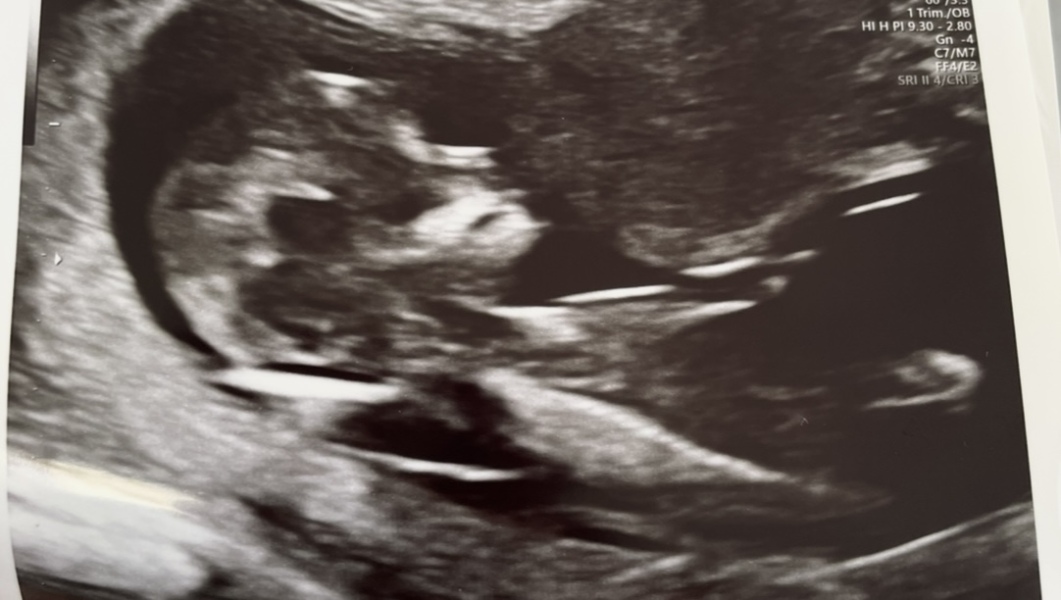

Any idea why risk so high? Scan pic below.